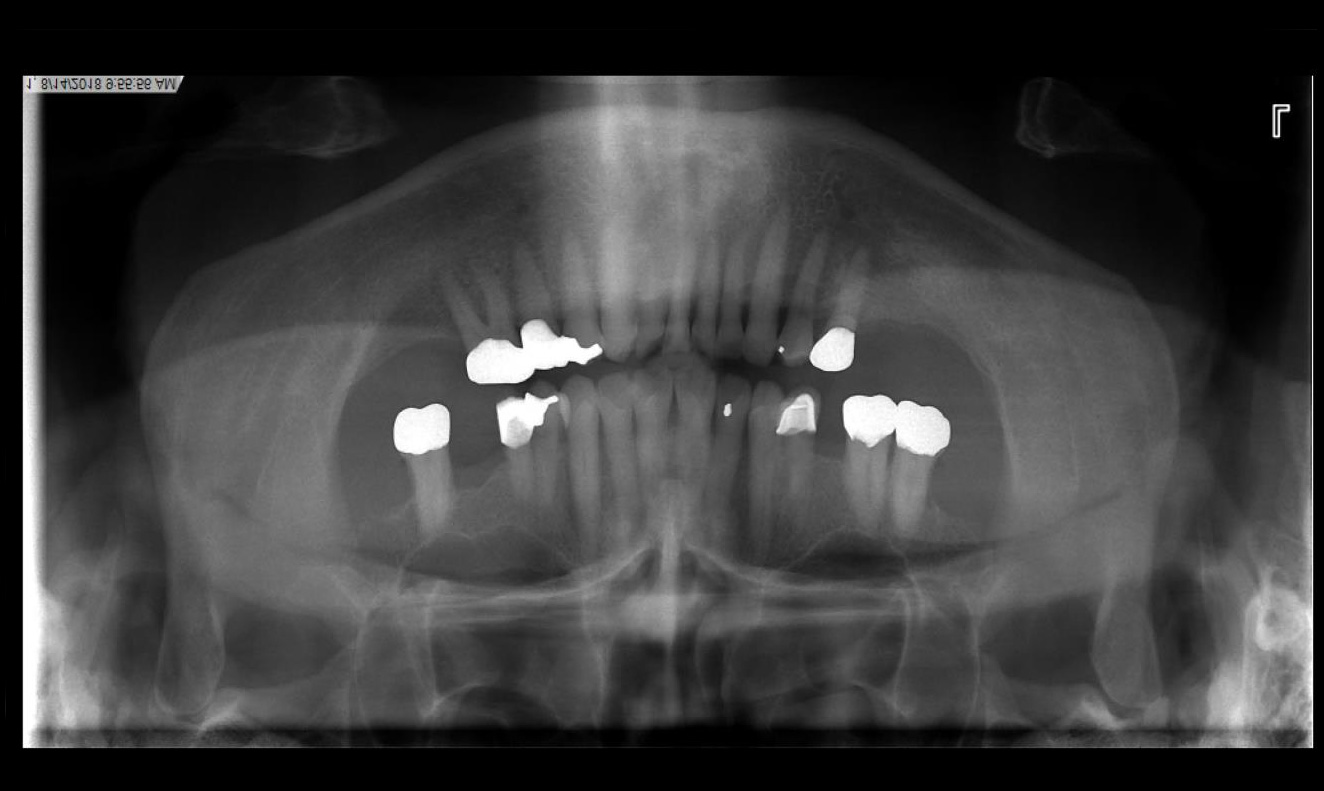

Radiographic evaluation: Full Mouth Series and Panoramic X-ray

- Missing teeth - #1,3, 13, 16, 17 18, 19, 31, 32

- Probing depths measured after extraction of supraerupted #2 and #15

| Unopposed upper molars leading to supraeruption (#2 and 15), difficulty chewing | Align teeth with occlusal plane and prevent further supraeruption or extract supraerupted teeth to improve the overall prognosis of oral health and prevent further supraeruption | Patient opts to go with extraction of supraerupted teeth. Patient is willing to pay for implants and is comfortable with the amount of time required to reach treatment goals. Alternative treatment includes intentional endo on supraerupted teeth and enameloplasty. Patient has had multiple failed endo treatments and is unwilling to go that route. |

- ext #s 2, 15